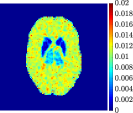

Finally, Figure 8 represents the last frame of the dynamic PET data reconstructed with the mean parametric values returned by reg-AS-TR, reg-GN, and lsqcurvefit, with respect to the noise-free, 10-noise, and 20-noise IFs.

In general, reg-AS-TR and lsqcurvefit seem to provide similar mean reconstructions, although uncertainties associated to lsqcurvefit are significantly bigger. On the other hand reg-GN seems to systematically underestimate the parameter values within region . Furthermore and as expected, for all methods the quality of the parametric reconstructions deteriorates with increasing noise levels; this is more clear from the and parametric images, probably due to the different sensitivities of the data with respect to the model parameters [37]. In reg-GN and lsqcurvefit some artifacts can be observed at the edges of the homogeneous regions, especially around region and region , whereas the effect of regularization in reg-AS-TR results in a reduced presence of artifacts while the structure of the regions is preserved. This general trend is confirmed by the error-bar plots of Figure 7. Finally, the frames in Figure 8 corresponding to reg-AS-TR show a significant improvement of the image quality with respect to what is provided by the other two approaches.